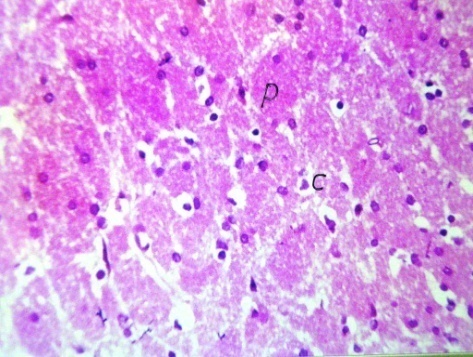

Microscopic examination of brain tissue sections of rats in the negative control group showed no histopathological alteration, with normal histological structure of the hippocampus (Fig.1). Photomicograph of brain tissue sections of rats in the AD-induced group showed neuronal degeneration and oedema with gliosis in the hippocampus (Fig.2). Also, cerebral encephalomelacia and plaques formation have been observed in the hippocampus of the AD-induced group (Fig. 3). Photomicograph of brain tissue sections of rats in the AD-induced group treated with rivastigmine showed intact normal histological structure of the hippocampus (Fig.4). Microscopic examination of brain tissue sections of rats in the AD-induced group treated with B. serrata (137.5 mg/kg b. wt) showed normal histological structure of hippocampus and striatum (Fig. 5). While, photomicrograph of brain tissue section of rats in the AD-induced group treated with B. serrata (68.75 mg/kg b. wt) showed neuronal degeneration and odema in the hippocampus (Fig. 6).

Photomicrograph of brain tissue sections of AD-induced rats showed neuronal degeneration and oedema with gliosis in the brain. Also, cerebral encephalomelacia and amyloid plaques formation have been detected in AD-induced rats. Klatzo et al. [82] stated that the intracerebral administration of Al in the experimental animals induced neurofibrillary degeneration and appearance of tangle-like structures that are similar to the NFTs found in the brains of AD patients. Praticó et al. [83] found that oral administration of Al caused marked increase in the amount of β-amyloid both in its secreted and accumulated forms. Also, Al could increase the deposition of senile plaques in AD-model mice transfected with human APP gene (Tg 2576). Rodella et al. [84] also in consistent with other study demonstrated that oral Al supplementation caused the accumulation of β-amyloid and impaired the spatial learning memory in AD-model mice.

Photomicrograph of brain tissue sections of AD-induced rats treated with rivastigmine revealed no histopathological alterations in the hippocampus. Coleman et al. [85] demonstrated that rivastigmine treatment in a primary cell culture model can not only preserve neurons, but preserve neuronal morphology and synaptic markers that are vital for normal neuronal function. Moreover, Bihaqi et al. [86] demonstrated normal histological appearance of the brain cells treated with rivastigmine tartrate. These authors stated that rivastigmine could reverse the histopathological alterations of the brain caused by Al.

Photomicrograph of brain tissue sections of AD-induced rats treated with with B. serrata (137.5 mg/kg b. wt) showed no histopathological alteration in the hippocampus and striatum. While, photomicrograph of brain tissue sections of AD-induced rats treated with B. serrata (68.75 mg/kg b. wt) showed neuronal degeneration and odema in the hippocampus. These results are in agreement with the results of Karima et al. [87] who revealed that boswellic acids could significantly enhance neurite outgrowth, branching and tubulin polymerization dynamics. It has been suggested that the enhancing effect of boswellic acid on microtubule polymerization kinetics might be the origin of increasing axonal outgrowth and branching. Also, Kirste et al. [88] found that boswellic acids significantly reduced cerebral edema measured by MRI in the study population.